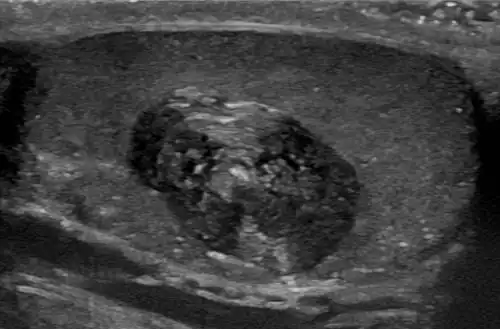

Epidermoid cyst in a testicle on ultrasound, with lamellated ("onion skin") appearance

Epidermoid cyst in a testicle on ultrasound, with lamellated ("onion skin") appearance -